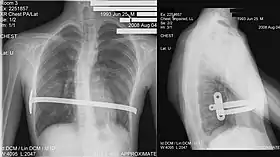

His procedure, widely known as the Nuss procedure, involves slipping in one or more concave steel bars into the chest, underneath the sternum. The bar is flipped to a convex position so as to push outward on the sternum, correcting the deformity. The bar usually stays in the body for about two years, although many surgeons are now moving toward leaving them in for up to five years. When the bones have solidified into place, the bar is removed through outpatient surgery. Although initially designed to be performed in younger children (less than 10 years of age) whose sternum and cartilage is more flexible, there are successful series of Nuss treatment in patients well into their teens and twenties. The Nuss procedure is a two-stage procedure.